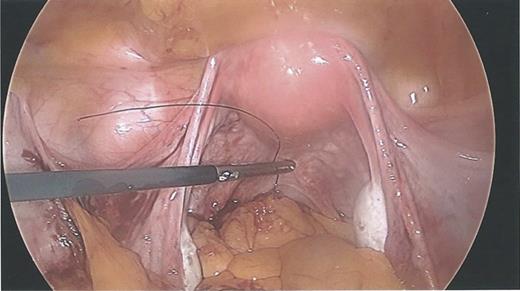

During the hysteroscopy 4 weeks later there was no evidence of an IUCD into the uterine cavity and no evidence of a perforation site in the uterus (Fig. 1). A laparoscopy followed, locating the coil threads deep in the Pouch of Douglas, with the IUCD perforating through the sigmoid colon into the lumen (Fig. 2). The IUCD was retrieved laparoscopically and the defect in the sigmoid colon was repaired by stapling the tear (Fig. 3).

Laparoscopy showing normal IUCD threads deep inside the Pouch of Douglas inside the sigmoid colon.